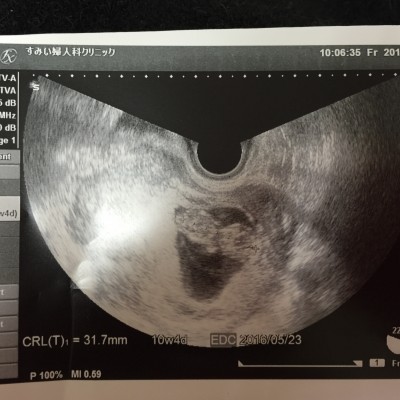

友達の紹介ですみい婦人科クリニックへ行きました。

無事に心拍が確認でき、

妊娠4ヶ月くらいになった頃、

すみい先生から「卒業ですね^^」と言われたときは、